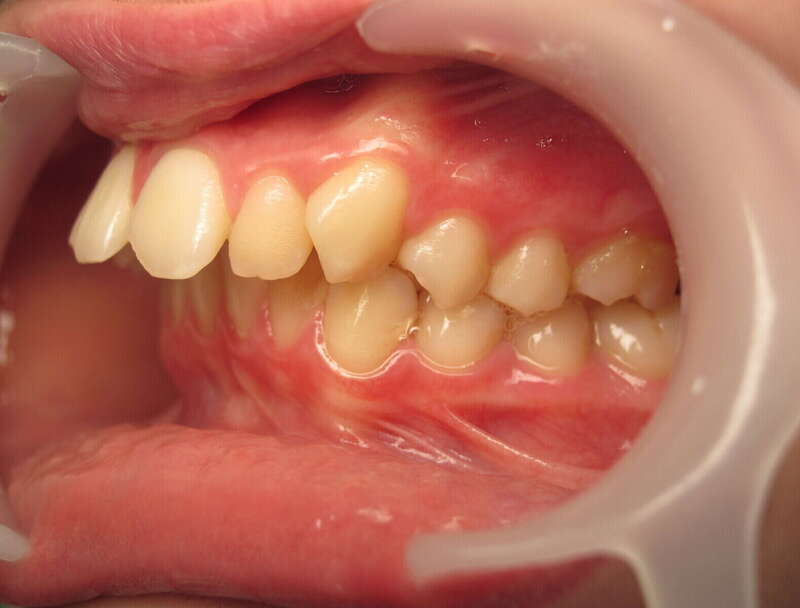

Cas n°1 traité par aligneurs (interception) - enfant

Ce cas d’interception chez un enfant de 8 ans démontre l'efficacité des aligneurs pour corriger des troubles fonctionnels précoces. Le diagnostic présentait des inversions d'articulé provoquant une déviation de la mandibule vers la gauche et un décalage des milieux.

Grâce à une coopération exemplaire et un traitement totalement indolore, l'expansion de l'arcade a permis de recentrer la mâchoire. Cette intervention a littéralement remis la croissance sur les rails, neutralisant le risque d'asymétrie faciale squelettique.